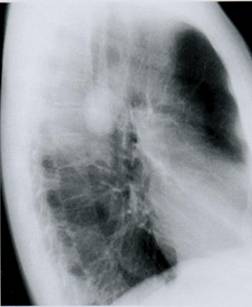

Мужчина 57 лет жалуется на сильный кашель, который сопро­вож­дается болью в грудной клетке, выделением мокроты со сгу­ст­кa­ми крови, длительное повышение температуры тела до 37,6оС, одыш­ку при умеренной нагрузке. В течение года похудел на 15 кг. Резкое ухуд­шение состояния отмечает в последние 2 месяца. Курит более 25 лет. На рентгенограммахоргановгруднойполости в 2-х стандартних проекциях, справа в области2 сегмента круглаятень с лучистыми контурами и дорожкой к корню легкого.

Для какого заболевания наиболее характерны вышеизложенные данные анамнеза и рентгенологического исследования:

A) Рак верхней доли правого легкого

B) Ателектаз правого легкого

C) Пневмоторакс

D) Хронический бронхит

E) Эмфизема легких

{Правильный ответ} = A